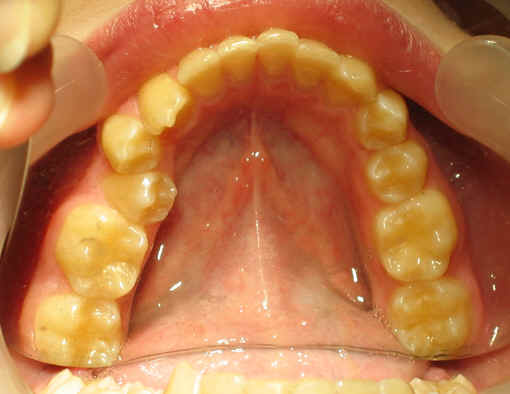

Malpositioned Premolar 13 year-old Caucasian boy

Pre-op 2009/04/18